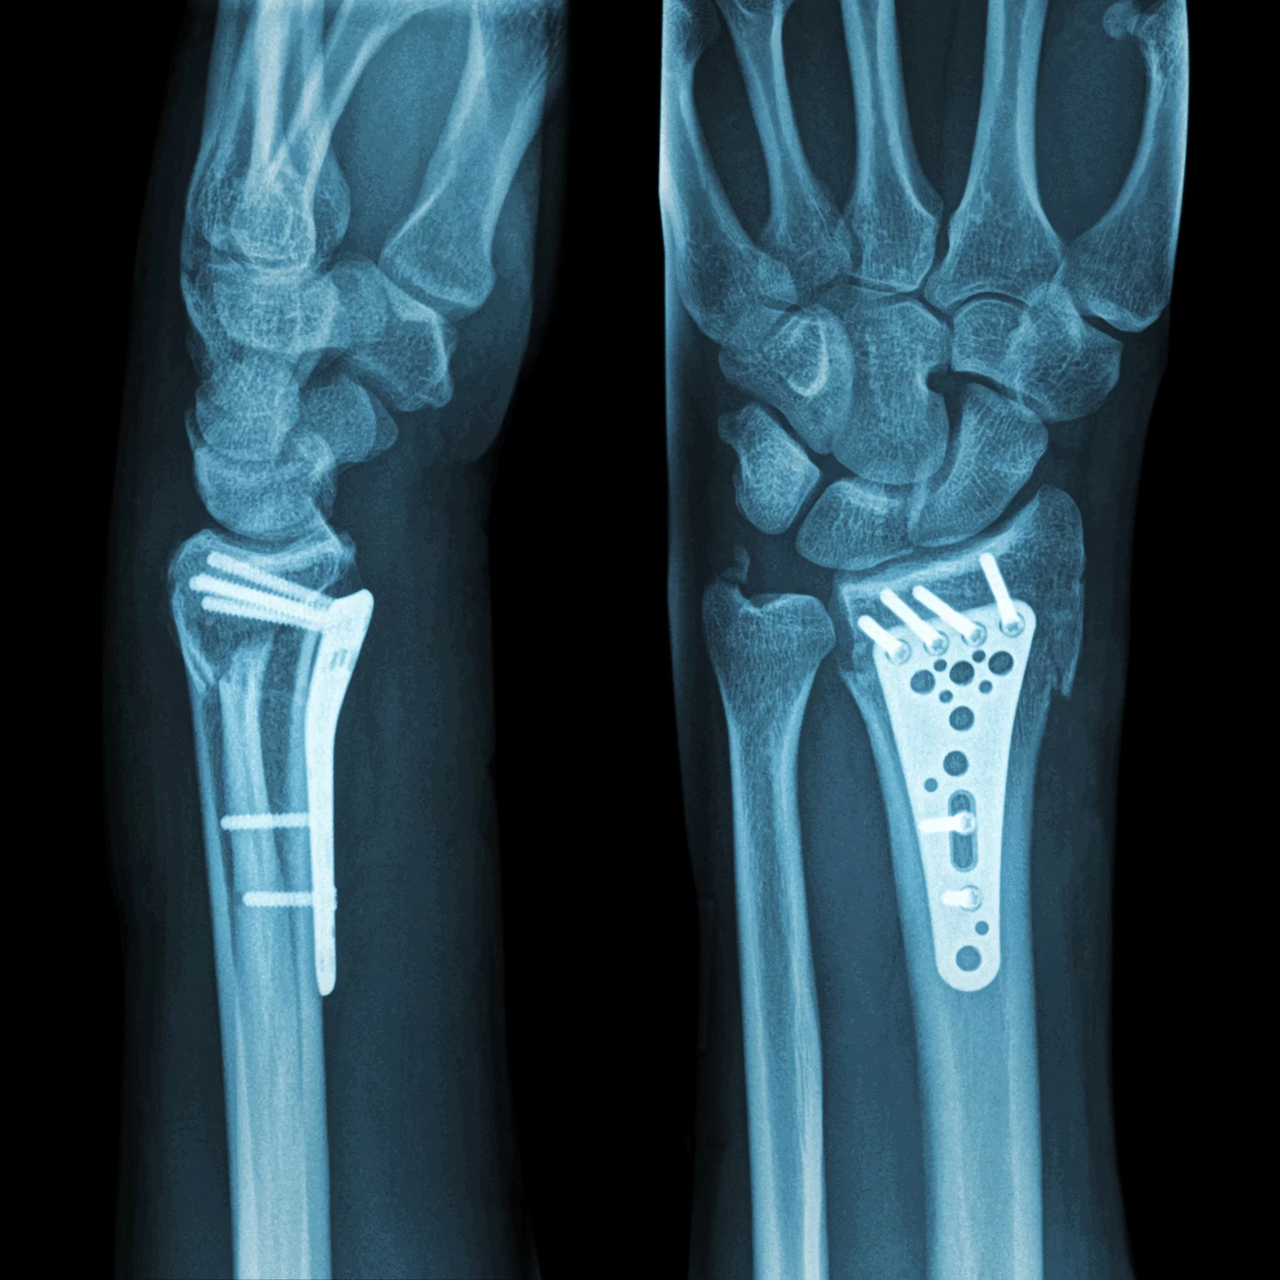

2. 수술적 치료

- 적용 대상: 복합 골절, 분쇄 골절, 관절면 침범 골절

- 치료 방법: 금속 핀·플레이트·나사로 뼈를 고정

- 고정 기간: 수술 후 깁스 또는 보조기 착용 약 6~8주

- 장점: 뼈를 정확히 맞출 수 있어 기능 회복률이 높음

- 단점: 수술 후 흉터, 감염 위험, 금속 제거 수술 가능성